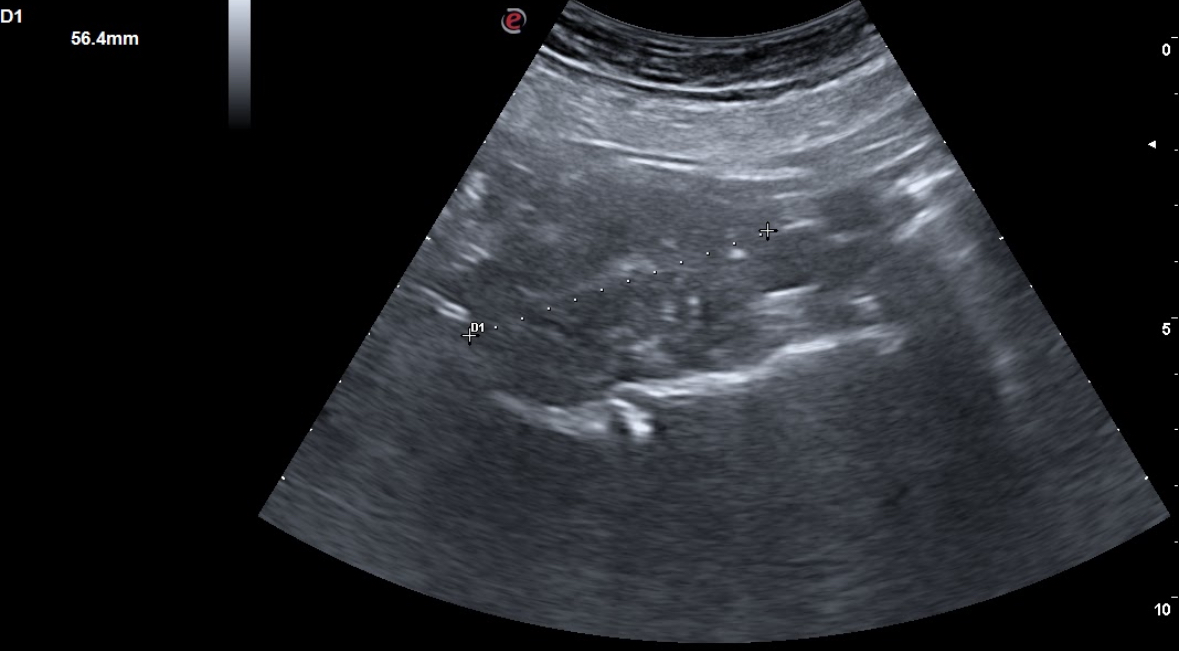

En consulta decidimos realizar ecografía clínica abdominal mostrando hígado de ecoestructura y tamaño adecuados, con vena porta y suprahepáticas permeables, con vesícula biliar repleccionada sin ecos en su interior, páncreas visible sin alteraciones, riñones con buena diferenciación córtico-medular con vejiga reflexionada sin ecos en su interior, útero involucionado, y una masa dependiente de fosa ilíaca derecha de 5×5 cm de ecoestructura similar a un riñón, correspondiente al área explorada.